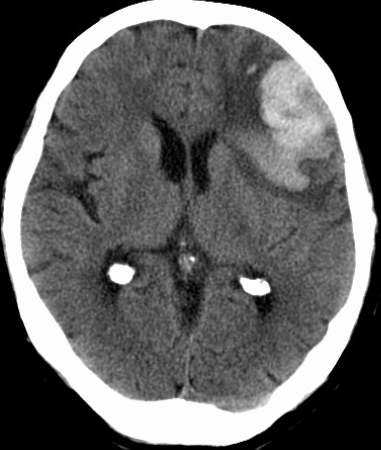

脑叶出血,又称皮质下出血,包括额叶、顶叶、颞叶和枕叶。

常见病因有:

颞叶出血

责任血管:大脑中动脉颞极动脉,大脑后动脉颞下前、颞下中、颞下后动脉

症状体征: